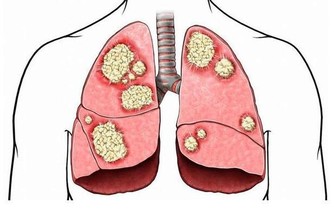

糖尿病是一種慢性進行性疾病,患者不是不能有更長的壽命,但這要求他們必須花更多時間來對付並發症。並不是說所有糖尿病患者都注定會出現並發症,而是說,你必須防止問題出現。

長期高血糖會對身體的許多器官造成傷害,但積極改變生活方式有助於降低血糖和預防糖尿病並發症。採取行動永遠不會太晚,即使你已經患有糖尿病很多年,仍然可以做出改變以改善健康狀況。